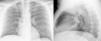

Paciente de 47 años con antecedentes de asma y exposición laboral a alérgenos de trigo (asma del panadero), en tratamiento con agonistas β2-adrenérgicos de acción corta a demanda (salbutamol en cartucho presurizado). Mientras trabajaba en la colocación de unas luces en su panadería, ante los síntomas de disnea, el paciente sacó del bolsillo el inhalador, que se encontraba sin el protector de la boquilla, y realizó una aplicación. Inmediatamente después presentó sensación de cuerpo extraño e incremento de su disnea, por lo que acudió al servicio de urgencias. La radiografía de tórax (fig. 1) mostró la presencia de un cuerpo extraño (bombilla tipo LED), alojado en el bronquio principal derecho. Ante los hallazgos radiológicos, el paciente fue trasladado a nuestro centro, donde se realizó su extracción mediante broncoscopio rígido. Tras interrogar de nuevo al paciente, este manifestó que guardaba el broncodilatador y varias bombillas en el mismo bolsillo de su ropa de trabajo.